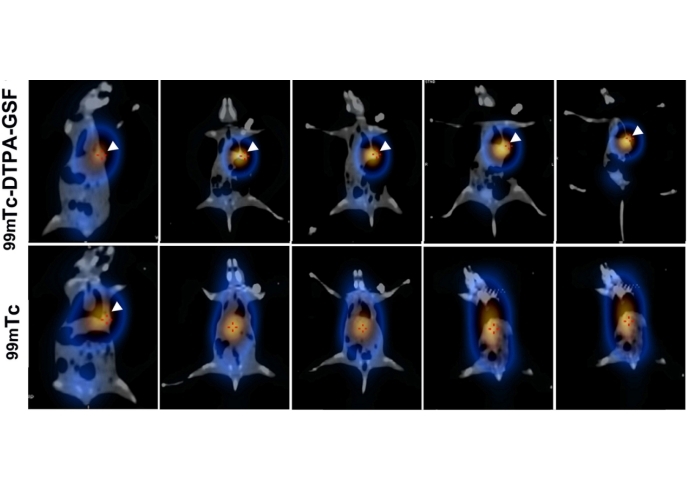

本发明公开了一种靶向ANGPT2的多肽及用于诊断脑胶质瘤的放射性分子探针。多肽的氨基酸序列如下所示:GSFIHSVPRH (甘氨酸-丝氨酸-苯丙氨酸-异亮氨酸-组氨酸-丝氨酸-缬氨酸-脯氨酸-精氨酸-组氨酸,Gly-Ser-Phe-Ile-His-Ser-Val-Pro-Arg-His)。本发明利用分子对接技术设计和筛选出与ANGPT2特异性结合的靶向多肽,填补了ANGPT2高亲和力多肽配体的空白;本发明制备的放射性核素标记分子探针作为脑胶质瘤的显像药物,具有显像时间长、容易制备等特点。